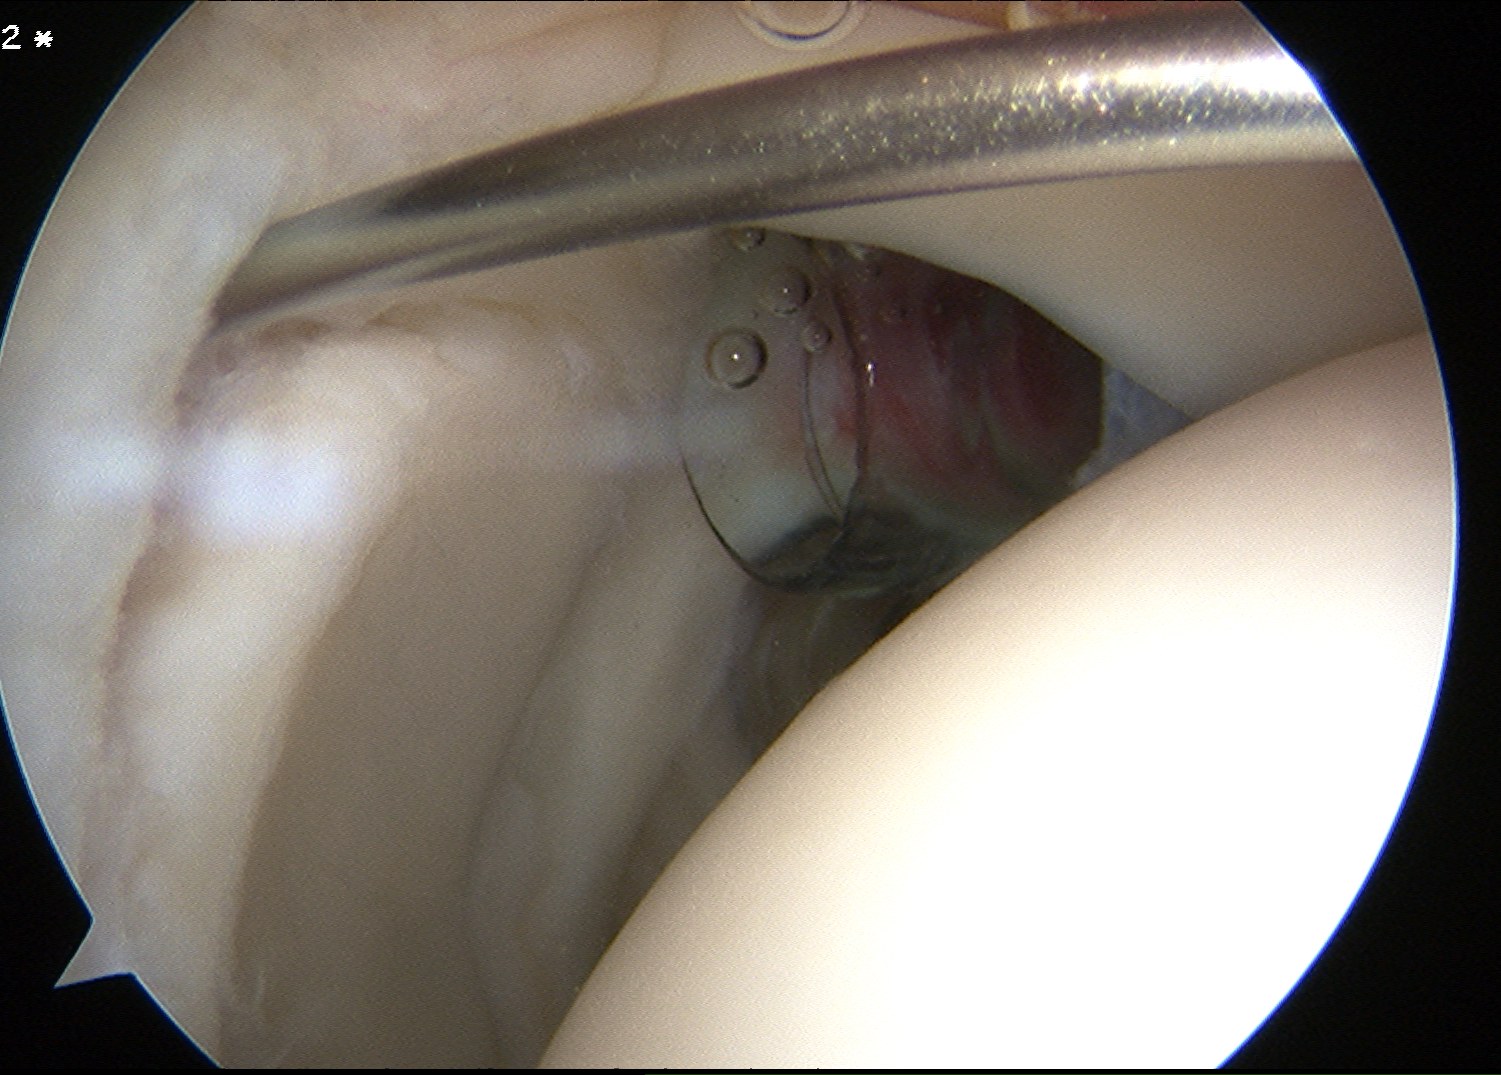

4. Dfficult posterior anchors

Camera through anterior / anterosuperiorlateral portal

A. Place anchor through posterior portal

- does not always give good angle

B. Trans infraspinatous Portal